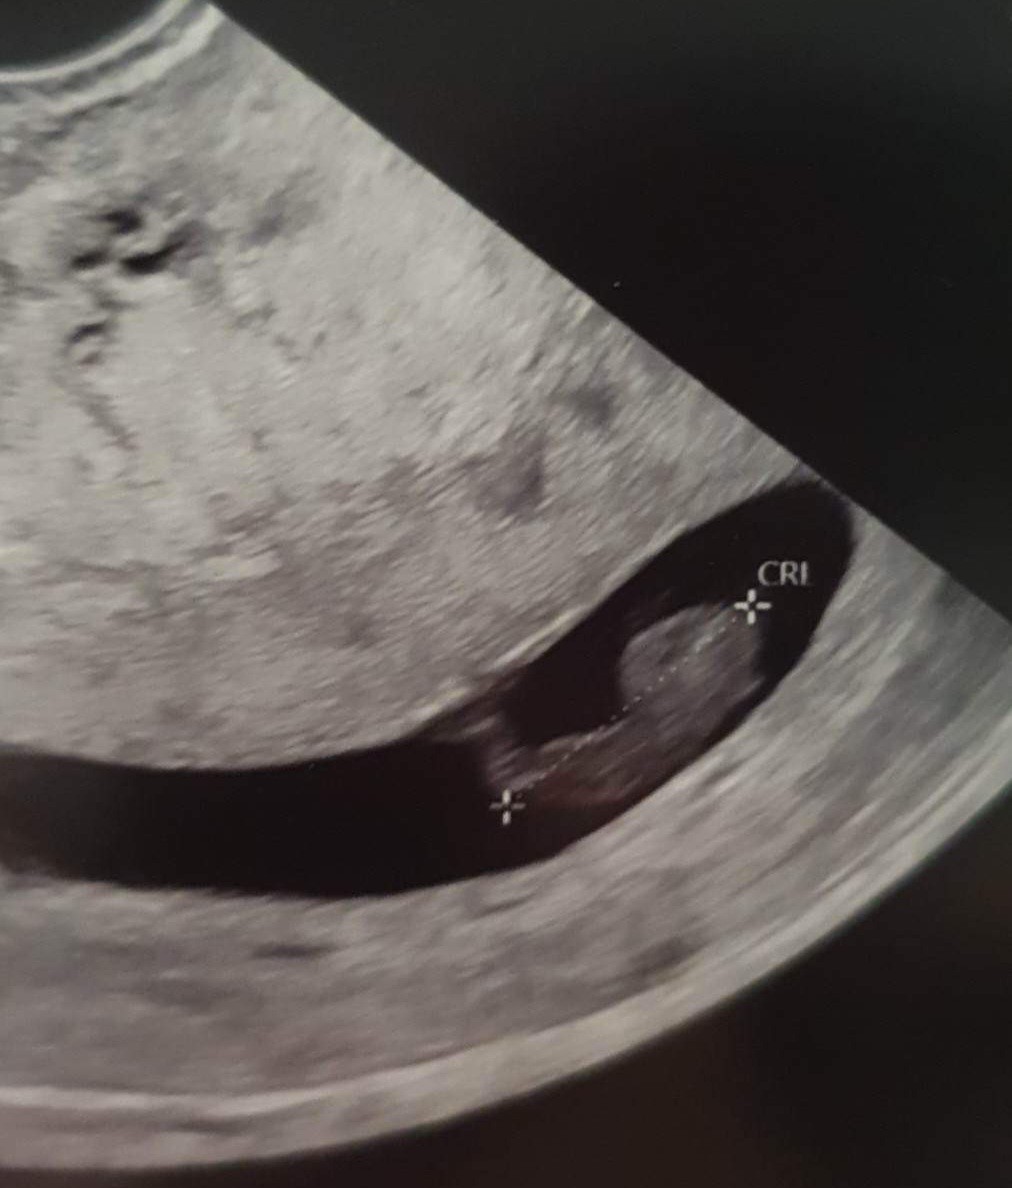

Jestem już po konsultacji wszystko wporzatku serduszko biję dzidzius rośnie:) podobno ten brązowy śluz może być od progreteronu dopochwowo oby już do końca bez żadnych niespodzianek i stresu.

Załączniki

• received_535214161783530.jpeg

received_535214161783530.jpeg

125 KB · Wyświetleń: 118